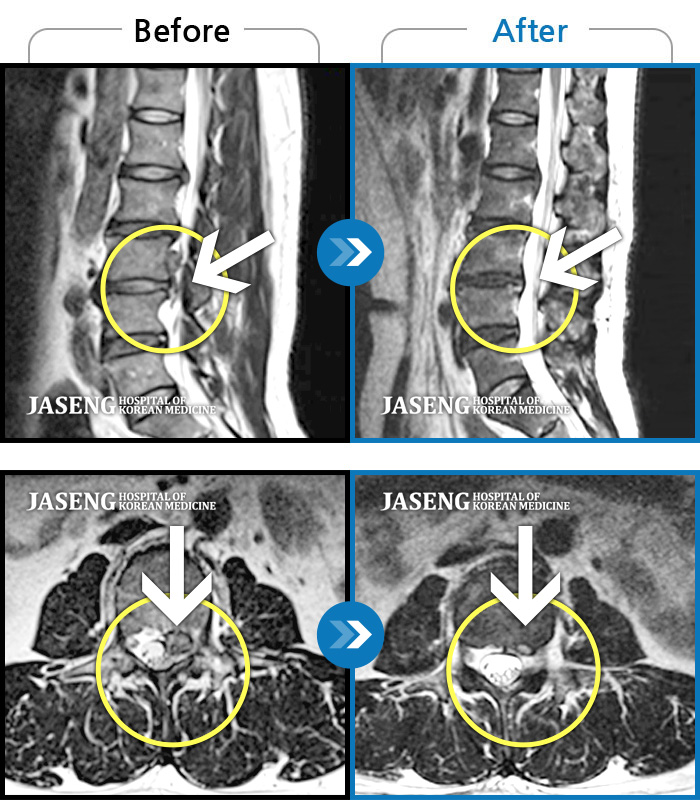

Xray 와 MRI 검사를 받았고

4번5번 척추사이 협착증과 유종이 원인이라고 하면서

침,약침, 한약복용으로 병행치료 받았으며,

신바로약침, 봉침, 청파전한약으로 한 달 정도 치료를 받으니 통증이 덜하고 점차 걸을 수 있는 거리가 늘어가기 시작하였다.

12월20일까지 두 달 정도 치료를 마친 결과,

거의 정상상태로 회복 되었으며, 현재는 집에서 꾸준하게 체조와 가벼운 운동으로 관리하고 있습니다.